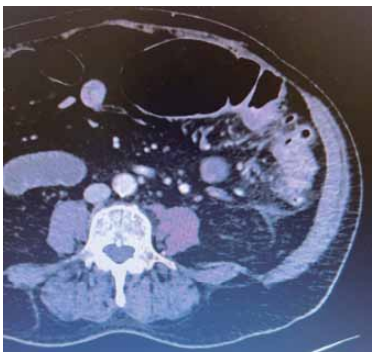

Paciente de 71 anos, sexo feminino, apresenta queixa de dor em hemiabdome esquerdo. Em bom estado geral, sem febre, vômito ou alterações do trato gastrointestinal. Ao exame físico, dor à palpação de flanco esquerdo com descompressão brusca interrogada.

Obteve-se a seguinte imagem na tomografia realizada na investigação:

Enunciado 4449355-1

(Arquivo pessoal; imagem utilizada com autorização)

Com relação ao caso, assinale a alternativa correta.